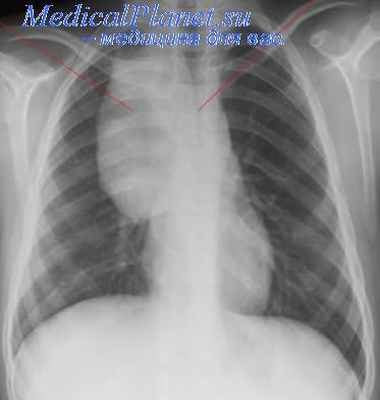

ЭКГ — синусовая аритмия с ЧСС 94 уд/мин (нормокардия). Диффузные изменения миокарда. УЗИ внутренних органов и почек без патологии. Рентгенография грудной клетки показала увеличение размеров сердца ( рис. 1 ).

Рис. 1. Рентгенограмма грудной клетки девочки Т., 9 лет. Иллюстрация В.Г. Молчанова, врача-рентгенолога ГАУЗ АО «Амурская областная детская клиническая больница»